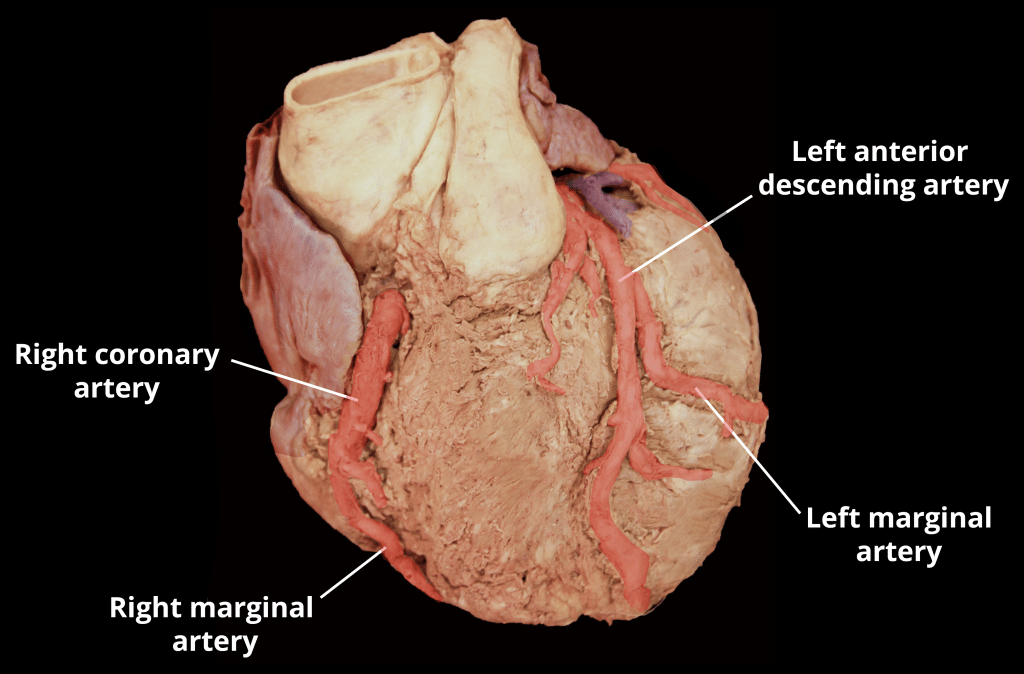

The entire body must be supplied with nutrients and oxygen via the circulatory system and the heart is no exception. The coronary circulation refers to the vessels that supply and drain the heart. Coronary arteries are named as such due to the way they encircle the heart, much like a crown. This article will outline the naming, distribution, and clinical relevance of vessels in the coronary circulation. Pro Feature - 3D Model You've Discovered a Pro Feature Access our 3D Model Library Explore, cut, dissect, annotate and manipulate our 3D models to visualise anatomy in a dynamic, interactive way. Learn More Naming Coronary Arteries There are two main coronary arteries which branch to supply the entire heart. They are named the left and right coronary arteries, and arise from the left and right aortic sinuses within the aorta. The aortic sinuses are small openings found within the aorta behind the left and right flaps of the aortic valve. When the heart is relaxed, the back-flow of blood fills these valve pockets, therefore allowing blood to enter the coronary arteries. The left coronary artery (LCA) initially branches to yield the left anterior descending (LAD), also called the anterior interventricular artery. The LCA also gives off the left marginal artery (LMA) and the left circumflex artery (Cx). In ~20-25% of individuals, the left circumflex artery contributes to the posterior interventricular artery (PIv). The right coronary artery (RCA) branches to form the right marginal artery (RMA) anteriorly. In 80-85% of individuals, it also branches into the posterior interventricular artery (PIv) posteriorly. By TeachMeSeries Ltd (2025) Fig 1Anterior view of the arterial supply to the heart. By TeachMeSeries Ltd (2025) Fig 2Overview of the branching structure of the coronary arteries. Cardiac Veins The venous drainage of the heart is mostly through the coronary sinus – a large venous structure located on the posterior aspect of the heart. The cardiac veins drain into the coronary sinus, which in turn, empties into the right atrium. There are also smaller cardiac veins which pass directly into the right atrium. The main tributaries of the coronary sinus are: Great cardiac vein (anterior interventricular vein) – the largest tributary of the coronary sinus. It originates at the apex of the heart and ascends in the anterior interventricular groove. It then curves to the left and continues onto the posterior surface of the heart. Here, it gradually enlarges to form the coronary sinus. Small cardiac vein – located on the anterior surface of the heart, in a groove between the right atrium and right ventricle. It travels within this groove onto the posterior surface of the heart, where it empties into the coronary sinus. Middle cardiac vein (posterior interventricular vein) – begins at the apex of the heart and ascends in the posterior interventricular groove to empty into the coronary sinus. Posterior cardiac vein – located on the posterior surface of the left ventricle. It lies to the left of the middle cardiac vein and empties into the coronary sinus. By TeachMeSeries Ltd (2025) Fig 3Anterior view of the venous drainage of the heart. Supplied by the great and small cardiac veins By TeachMeSeries Ltd (2025) Fig 4Posterior view of the heart, showing the venous drainage. Pro Feature - Dissection Images Anterior view of the coronary arteries. Anterior view of the coronary arteries. You've Discovered a Pro Feature Access our Dissection Image Library Enhance your understanding with high-resolution dissection images showcasing real-life anatomy. Learn More Distribution of the Coronary Arteries In general, the area of the heart which an artery passes over will be the area that it perfuses. The following describes the anatomical course of the coronary arteries. See Appendix A for a tabular overview of the arterial distribution. The RCA passes to the right of the pulmonary trunk and runs along the coronary sulcus before branching. The right marginal artery arises from the RCA and moves along the right and inferior border of the heart towards the apex. The RCA continues to the posterior surface of the heart, still running along the coronary sulcus. The posterior interventricular artery then arises from the RCA and follows the posterior interventricular groove towards the apex of the heart. The LCA passes between the left side of the pulmonary trunk and the left auricle. The LCA divides into the anterior interventricular branch and the circumflex branch. The anterior interventricular branch (LAD) follows the anterior interventricular groove towards the apex of the heart where it continues on the posterior surface to anastomose with the posterior interventricular branch. The circumflex branch follows the coronary sulcus to the left border and onto the posterior surface of the heart. This gives rise to the left marginal branch which follows the left border of the heart. By TeachMeSeries Ltd (2025) Fig 4Anterior view of territorial arterial supply to the heart. By TeachMeSeries Ltd (2025) Fig 5Posterior view of territorial arterial supply to the heart. Clinical Relevance Coronary Artery Disease Coronary artery disease or coronary heart disease (CHD) is a leading cause of death, both in the UK and worldwide. It describes a reduction in blood flow to the myocardium and has several causes and consequences. CHD can result in reduced blood flow to the heart as a result of narrowing or blockage of the coronary arteries. This may be due to atherosclerosis, thrombosis, high blood pressure, diabetes or smoking. All these factors lead to a reduced flow of blood to the heart through physical obstruction or changes in the vessel wall. Angina pectoris is one consequence of CHD. Angina pectoris describes the transient pain a person may feel on exercise as a result of lack of oxygen supplied to the heart. This pain is felt across the chest but is quickly resolved upon rest. Exercise is a trigger for angina as the coronary arteries fill during the diastolic period of the cardiac cycle. On exercising, the diastolic period is shortened meaning that there is less time for blood flow to overcome a blockage in one of the coronary vessels in order to supply the heart. If left untreated, angina can soon progress to more severe consequences, such as a myocardial infarction. The sudden occlusion of an artery results in infarction and necrosis of the myocardium. This means a section of the heart is unable to beat (which part of the heart depends on which artery has become occluded). The ECG leads on which an MI change appears can be used to locate the artery that had been occluded as shown in the table. Description ECG leads with changes Artery occluded Inferior II, III, aVF RCA Anteroapical V3 and V4 Distal LAD Anteroseptal V1 and V2 LAD Anterolateral I, aVL, V5 and V6 Circumflex artery Extensive anterior I, aVL, V2-V6 Proximal LCA True posterior Tall R in V1 RCA Diagnosis and Treatment of Coronary Artery Disease By Maria A Pantaleo et al [CC-BY-2.0] via Wikimedia Commons Fig 1.6A coronary angiogram. Two critical narrowings have been labelled. A blockage in a coronary artery can be rapidly identified by performing a coronary angiogram. The imaging modality involves the insertion of a catheter into the aorta via the femoral artery. A contrast dye is injected into the coronary arteries and x-ray based imaging is then used to visualise the coronary arteries and any blockage that may be present. Immediate treatment of a blockage can be performed by way of a coronary angioplasty, which involves the inflation of a balloon within the affected artery. The balloon pushes aside the atherosclerotic plaque and restores the blood flow to the myocardium. The artery may then be supported by the addition of an intravascular stent to maintain its volume. Appendix A – Tabular Overview of the Vasculature of the Heart Artery Region supplied Vein draining region Right coronary Right atrium SA and AV nodes Posterior part of interventricular septum (IVS) Small cardiac vein Middle cardiac vein Right marginal Right ventricle Apex Small cardiac vein Middle cardiac vein Posterior interventricular Right ventricle Left ventricle Posterior 1/3 of IVS Left posterior ventricular vein Left coronary Left atrium Left ventricle IVS AV bundles Great cardiac vein Left anterior descending Right ventricle Left ventricle Anterior 2/3 IVS Great cardiac vein Left marginal Left ventricle Left marginal vein Great cardiac vein Circumflex Left atrium Left ventricle Great cardiac vein Rate This Article